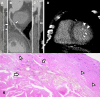

SARS-CoV-2 infection, responsible for COVID-19 outbreak, can cause cardiac complications, worsening outcome and prognosis. In particular, it can exacerbate any underlying cardiovascular condition, leading to atherosclerosis and increased plaque vulnerability, which may cause acute coronary syndrome. We review current knowledge on the mechanisms by which SARS-CoV-2 can trigger endothelial/myocardial damage and cause plaque formation, instability and deterioration. The aim of this review is to evaluate current non-invasive diagnostic techniques for coronary arteries evaluation in COVID-19 patients, such as coronary CT angiography and atherosclerotic plaque imaging, and their clinical implications. We also discuss the role of artificial intelligence, deep learning and radiomics in the context of coronary imaging in COVID-19 patients.